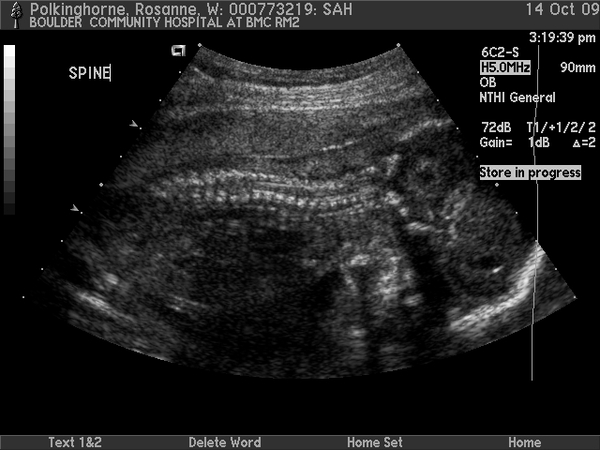

Sam in utero